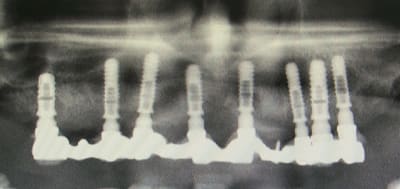

2010 bridge provisoire sur ANKYLOS, extaction, mise en charge immédiate bridge provisoire à armature métal sans scellement en 1 seul temps chiurgical.

Chirurgie à PAMIERS, préparation prothétique et dispositif de forage à MONTASTRUC LA CONSEILLERE, dans notre belle campagne de France.